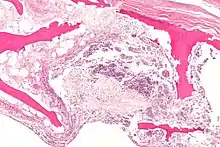

![]() | |

| X-ray of hip with femoral head osteonecrosis | |